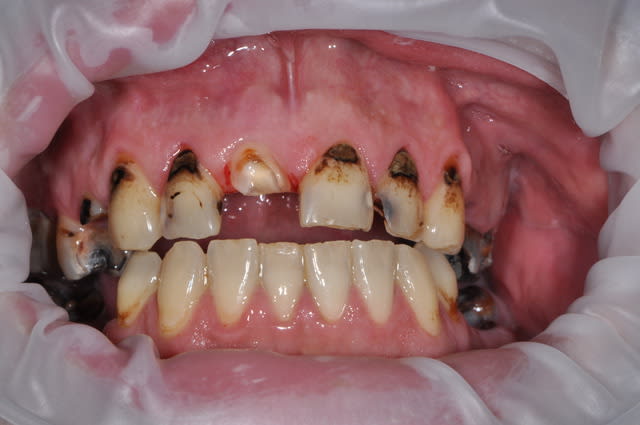

20 ans et toutes ses dents ! A la CMU de générations en générations....... status incomplet de 2003, et l'autre aujourd'hui 8 ans après. Et en 2003 avait poursuivi ses soins avec un lapin! ) On voit ce que donnent les dents dévitalisées et non couronnées dans le temps ) les autres aussi d'ailleurs ! ) C'est de la faute aux mauvais dentisss mon cousin !

Ceci dit c'est pas une star qui a couronné 31 et 41 )